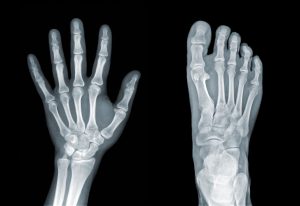

El Parmakları ve Ayak Eklemlerinde Kireçlenme

- El parmak eklemlerinde şişlik, nodül oluşumu ve estetik bozukluklar görülür

- Yazı yazma, düğme ilikleme gibi ince motor becerilerde zorluk yaşanır

- Ayak başparmağında (halluks rigidus) hareket kısıtlılığı ve yürüme bozuklukları ortaya çıkar

- Kavrama gücünde azalma günlük yaşam kalitesini düşürür